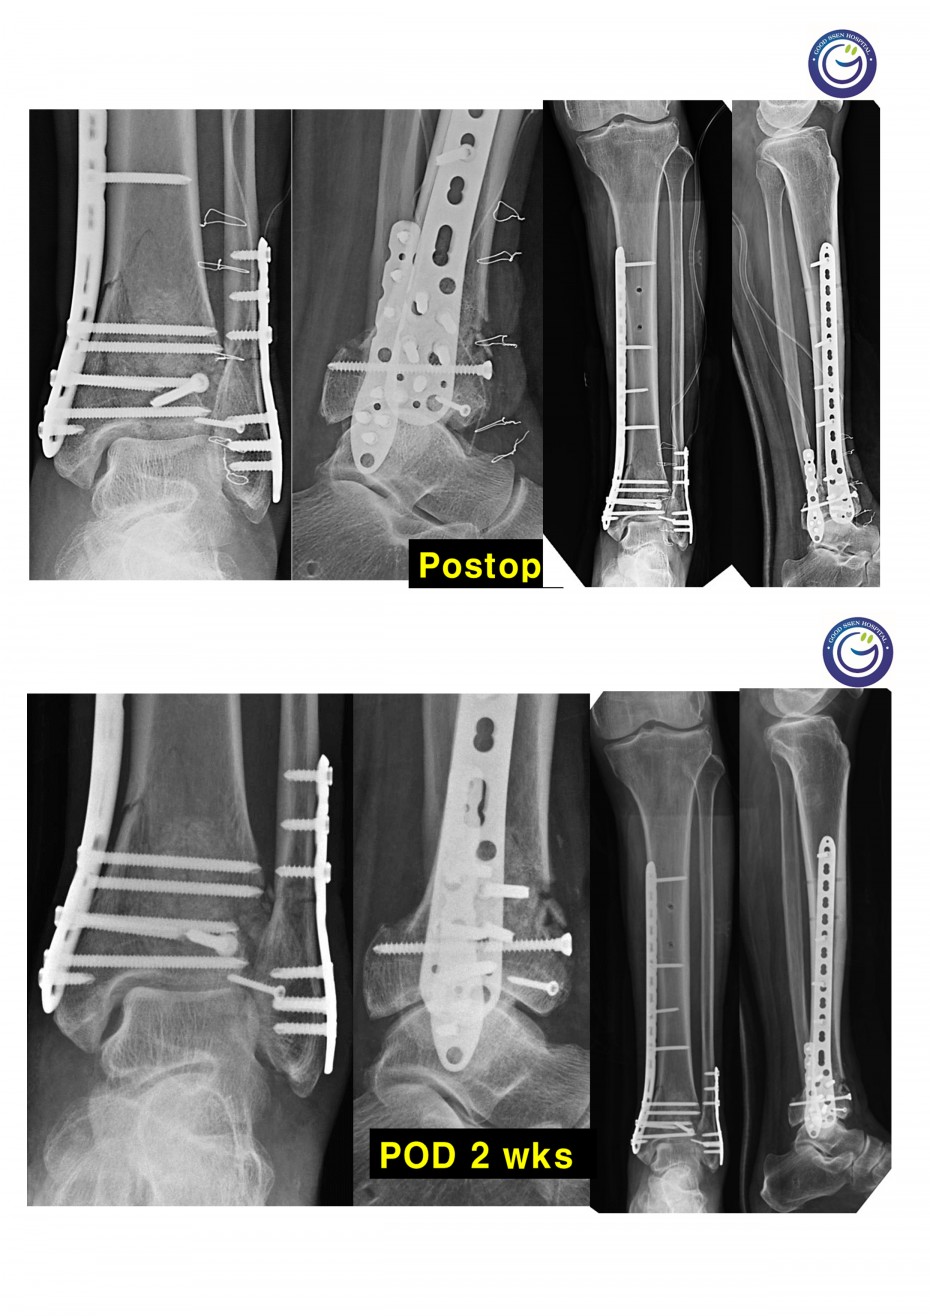

관절을 침범하는 심한 분쇄골절

절개없이 고정하는 최소침습적 고정방법 (MIPO)